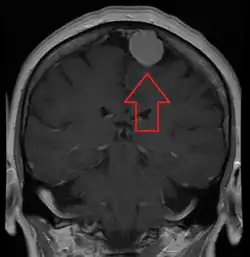

An MRI of the brain, demonstrating the appearance of a meningioma

Meningiomas are visualized readily with contrast CT, MRI with gadolinium,[23] and arteriography, all attributed to the fact that meningiomas are extra-axial and vascularized. CSF protein levels are usually found to be elevated when lumbar puncture is used to obtain spinal fluid. On T1-weighted contrast-enhanced MRI, they may show a typical dural tail sign absent in some rare forms of meningiomas.[18]